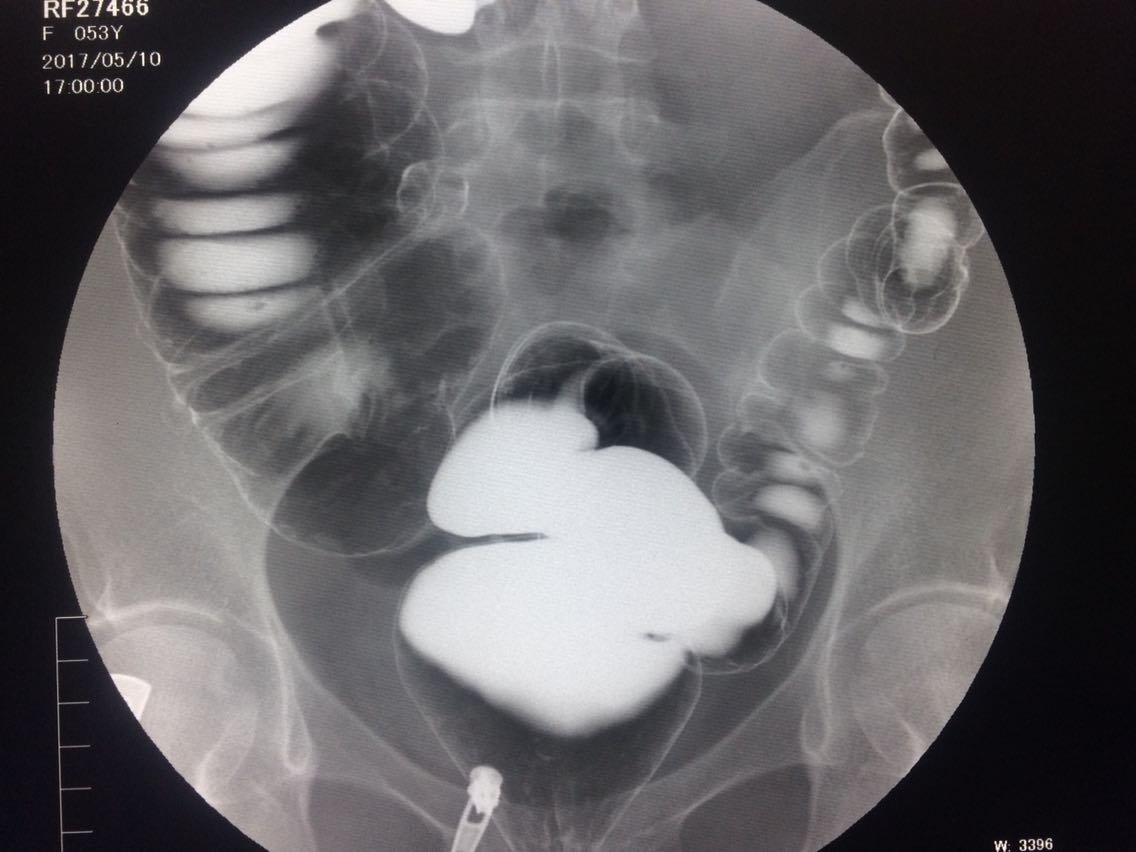

间断右下腹疼痛6年余。 6年来,无诱因出现右下腹痛,间断发生,呈胀痛,可忍受,压痛,无反跳痛。 既往:3年前,做肠镜未见明显异常。

查体,右下腹压痛。 入院做钡灌肠造影。

考虑升结肠占位。 完善术前各项检查。手术治疗。